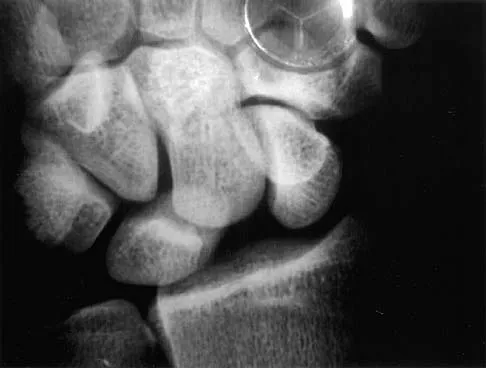

A 25-year-old construction worker lands on his outstretched hand in a fall. The position of his wrist at the time of impact causes a force that leads to hyperextension, ulnar deviation, and intercarpal supination. Radiographs are shown in Figures 48a and 48b. Management should consist of

Explanation